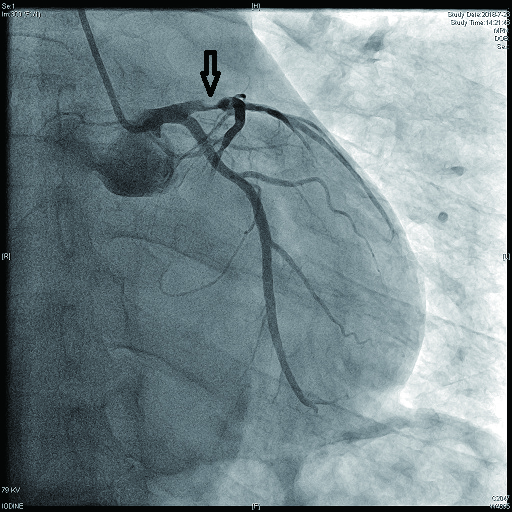

2 结果 本研究收集7例De winter综合征患者,6例进行了急诊冠脉造影,胸痛至球囊扩张平均时间为3.3 h,1例进行择期冠脉造影。其中,3例为前降支近段严重病变,1例为第一对角支闭塞,3例为前降支中段闭塞,2例合并多支血管病变,5例为单支血管病变,均行前降支支架植入术(表 4)。1周内行心脏彩超检查,4例出现室壁运动减弱,2例EF值小于50%,2例心脏形态结构未见异常,1例患者术后第2天因个人原因自动出院,未完善心脏彩超(表 5)。观察7例患者住院期间心电图演变情况,其中有3例在PCI术后出现前壁导联ST段抬高,4例未出现ST段抬高(表 5)。病例1住院期间出现室性心动过速,病例7患在急诊科就诊时发生呼吸心搏骤停,经抢救后送导管室行急诊冠脉造影。另外,所有患者经药物及介入治疗后,均症状缓解出院,院外长期服用阿司匹林100 mg/d+替格瑞洛90 mg/12 h+阿托伐他汀40 mg/瑞舒伐他汀20 mg等药物,出院1个月后电话随访,7例患者均无胸痛、气促发作及再住院,无死亡病例。

| 病例4 |

是 |

3 |

LAD中段及D1(图 11) |

LAD 85%及D1闭塞 |

0级 |

LAD中段植入支架1枚 |

| 病例5 |

| 注:LAD为左冠状动脉前降支; TIMI为心肌梗死溶栓治疗 |

表 5 7例患者的心电图演变及心脏彩超结果

| 编号 |

心电图是否演变为ST段抬高 |

心脏彩超 |

| 病例4 |

否 |

心脏形态结构未见异常,EF 63% |

De winter综合征表现为T波高尖,临床上应注意与急性心肌梗死超急性期、高钾等疾病相鉴别。有学者认为,De winter综合征不会演变成STEMI,与STEMI超急性期的鉴别关键在于密切监测心电图,如果是De winter综合征,其ST段不会抬高,而急性心肌梗死超急性期心电图会有动态演变,T波高尖之后会逐渐出现ST段抬高,R波下降甚至丢失,病理性Q波形成等特点,但这种观点与本研究观察到的情况不符,本文中病例1、病例5和病例6都观察到心电图演变为STEMI。临床上观察不到的原因可能是:⑴患者发病时间短,心电图还来不及演变为ST段抬高,就已行冠脉造影及支架植入开通血管。⑵ST段抬高可能是一过性的,开通血管后ST段又回落至基线。只有密切监测心电图,才可能真正发现问题。至于与高钾导致的T波高尖的鉴别,急查血清钾即可明确。De winter等[1]发现心电图表现为ST段上斜型压低,T波高尖的患者,冠脉造影均提示前降支近段闭塞,且为单支血管病变。本文中观察到,3例为前降支近段严重病变,1例为第一对角支闭塞,3例为前降支中段闭塞,2例合并多支血管病变,5例为单支血管病变。亦有研究发现,心电图表现为De winter综合征,但冠脉造影却提示左主干闭塞[8]。可见,本文的发现及Murat等[8]的发现提示De winter综合征的靶病变不一定局限于LAD近段。另外,从本文观察到的情况,患者发病年龄都相对年轻,且均为男性,2例合并高脂血症,与以往文献报道[9]相符。